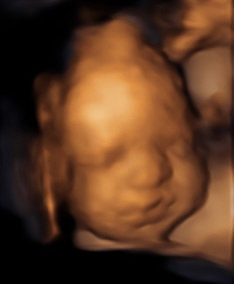

Our excitement and anticipation for Luna led us to document every stage she goes through. At 12 weeks you can see our angel was almost the size of a lime... Then, at 20 weeks, she grew into a good-sized fig. Upon arriving, our Luna will hopefully be the fully-grown Melon she’s meant to be! You can check out her journey here. We want everyone to be part of the amazing ride we are going through!